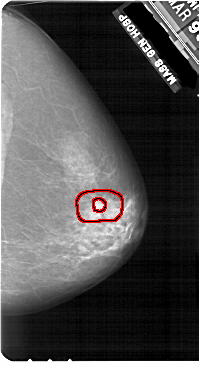

A_1908_1.LEFT_CC

RIGHT_CC LINES 5491 PIXELS_PER_LINE 2971 BITS_PER_PIXEL 12 RESOLUTION 43.5 OVERLAY

FILE: A_1908_1.RIGHT_CC.OVERLAY

TOTAL_ABNORMALITIES 1

ABNORMALITY 1

LESION_TYPE MASS SHAPE IRREGULAR MARGINS SPICULATED

ASSESSMENT 5

SUBTLETY 4

PATHOLOGY MALIGNANT

TOTAL_OUTLINES 2

BOUNDARY

CORE